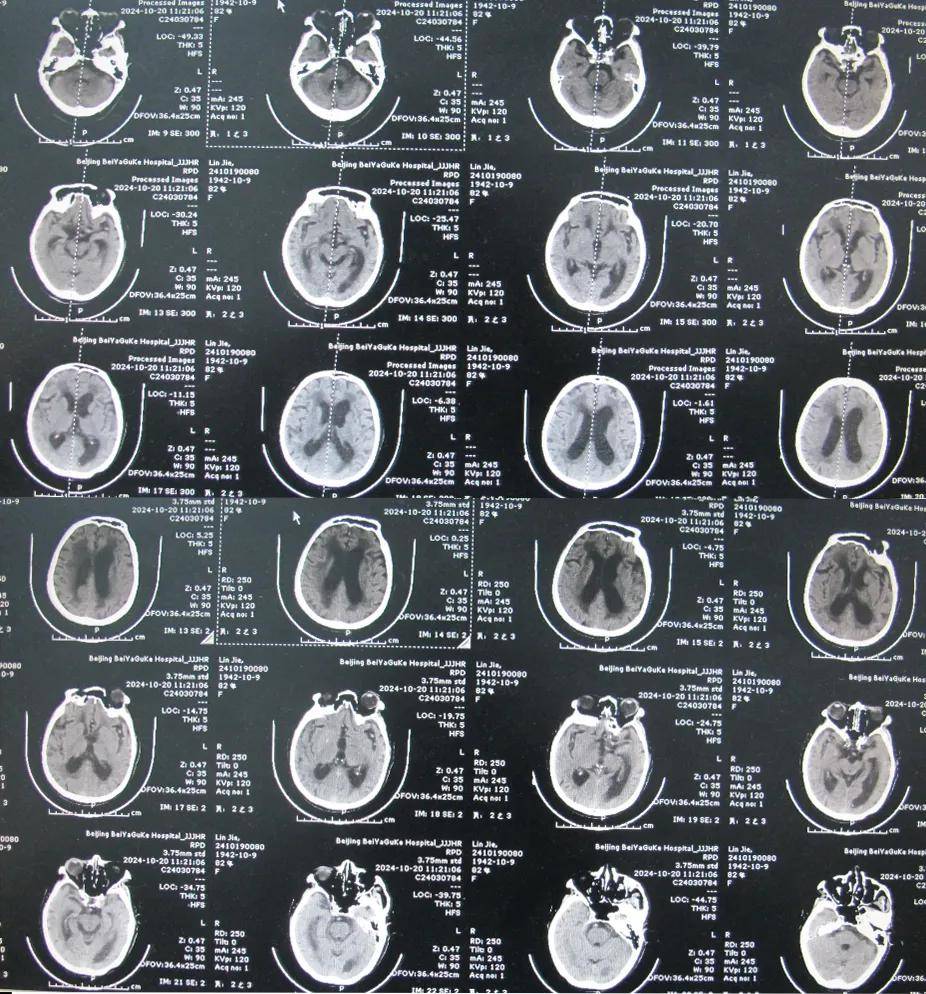

82岁脑出血后脑积水,北京某脑科医院治反致感染后19个月仍走路不稳

图-6:2024年10月19日头颅ct入院时头颅ct示双侧额顶枕叶及颞叶脑损伤

图-9:2018年1月11日头颅ct住院后9天即2018年1月17日,引流出淡黄色